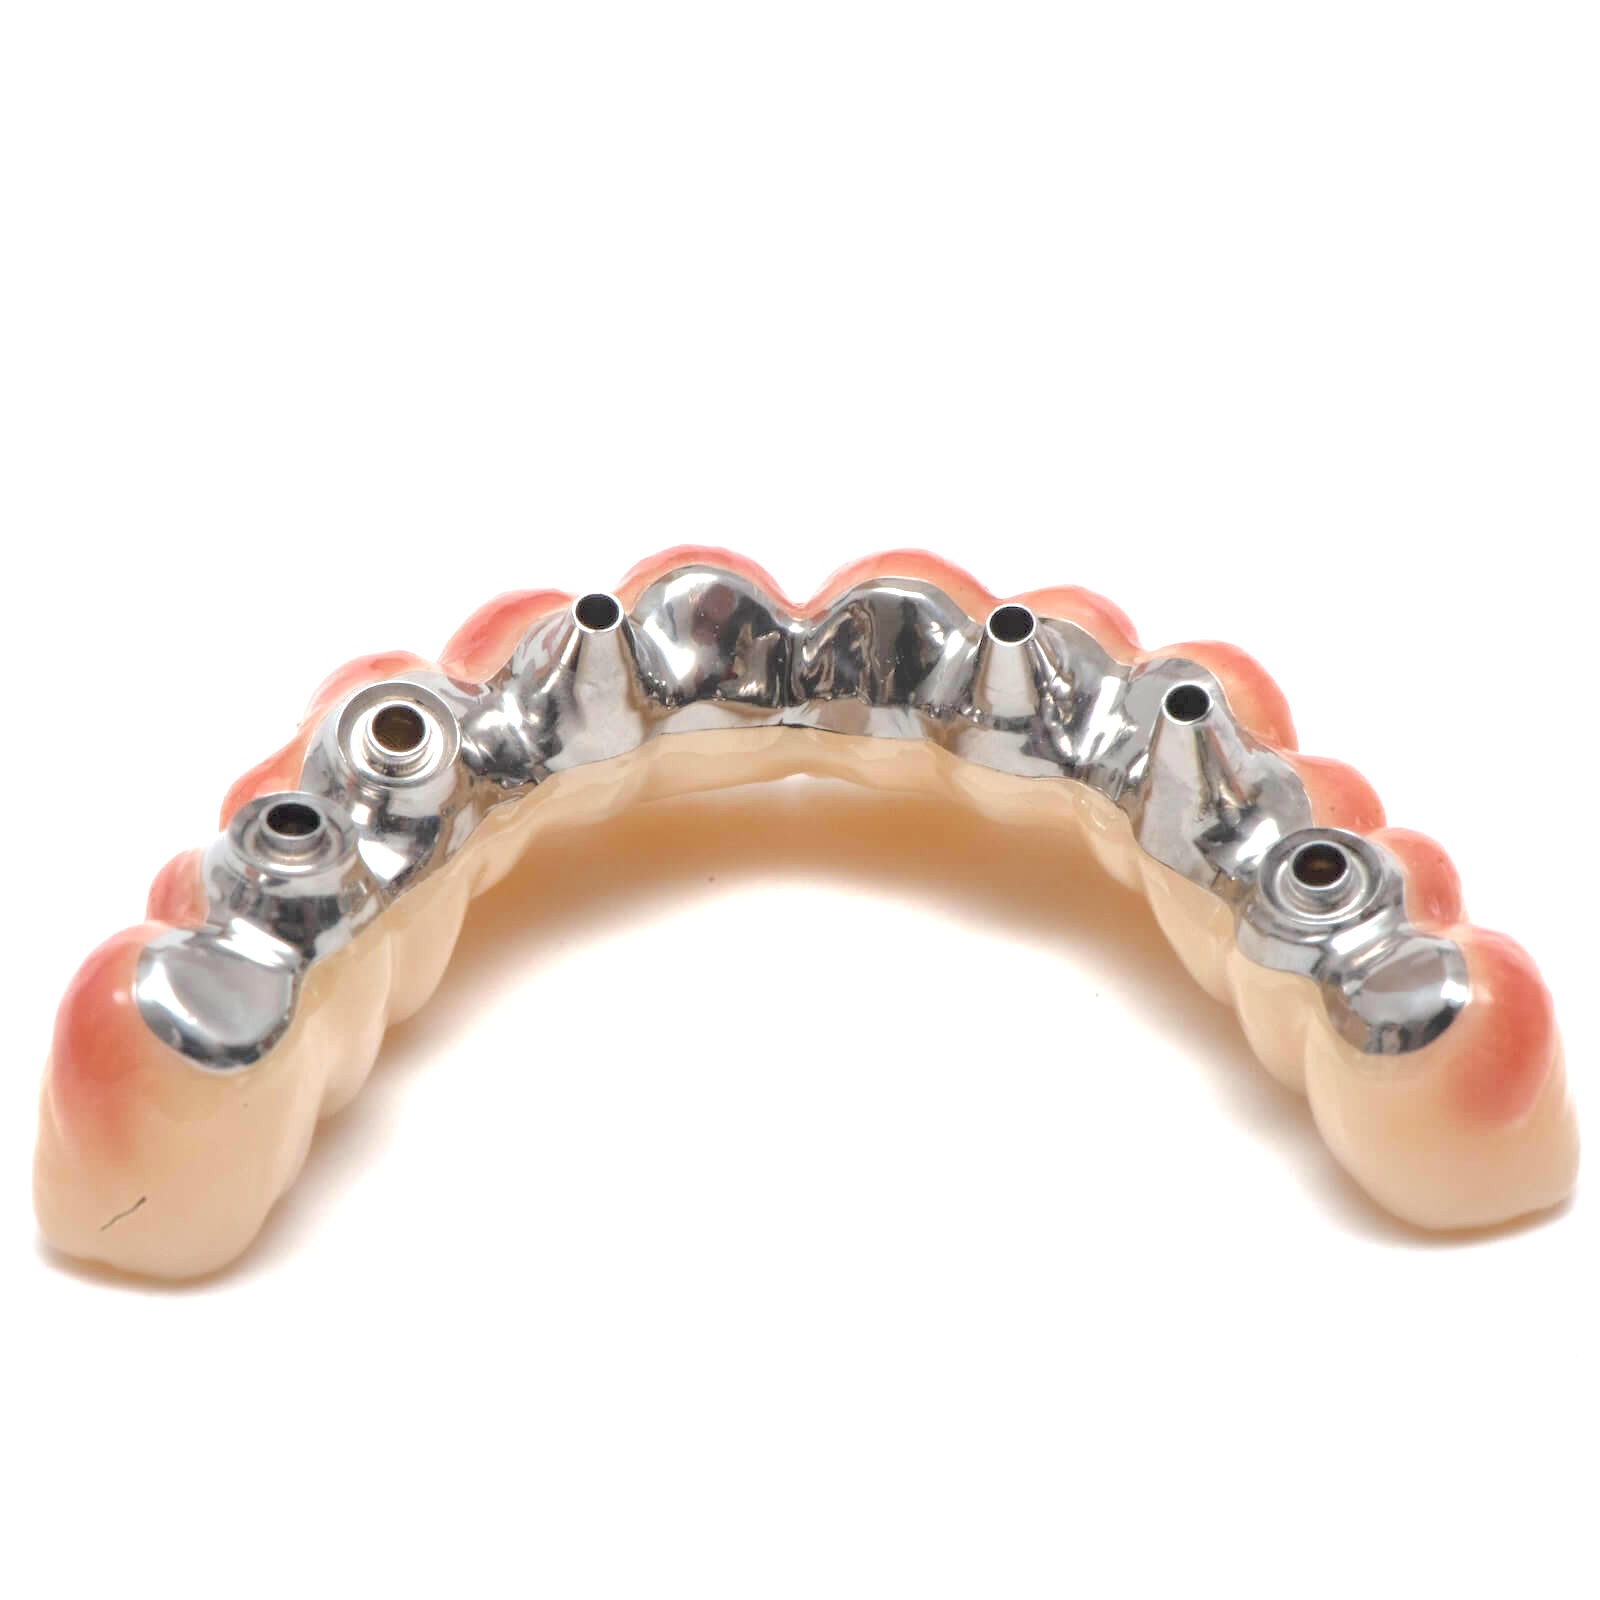

Dokonalá přesnost spojení

Při CAM zpracování musí být zuby i konstrukce navrženy a vyfrézovány tak, aby do sebe dokonale zapadly bez nutnosti velkých úprav při finálním sestavení.

Přesnost titanové konstrukce

Kontrola pasivního dosedu

Před jakýmkoliv zásahem je nutné zkontrolovat, zda konstrukce pasivně sedí na všech implantátech.

Kontrola a úpravy pod mikroskopem

Veškeré úpravy titanové konstrukce je nutné provádět výhradně pod mikroskopem. Zajišťuje to maximální přesnost bez rizika změny geometrie dosedu nebo snížení stability konstrukce.

Precizní leštění dosedových ploch

Každý dosed titanové konstrukce na gingivu musí být precizně vyleštěn do vysokého lesku. Plochy musí být hladké, bez podsekřivých částí, aby je pacient mohl snadno udržovat čisté přímo v ústech.

Spojení konstrukce se zuby

Lepení zubů ke konstrukci

Zuby frézované z kompozitu nebo jiného materiálu jsou osazeny do konstrukce a fixovány pomocí speciálních adhezivních kompozitních lepidel.

Odstranění lepidla

Přebytečné lepidlo se odstraní před finálním vytvrzením..

Modelace gingivy

V případě potřeby se na konstrukci modeluje červená estetika – umělá gingiva – pomocí speciálního růžového kompozitu.

Konečná úprava a kontrola

Pískování dosedů do implantátů

Ke konečnémů pískování se používají kulaté perly, které povrch titanové konstrukce vyčistí a vyleští.

Oparné zahlazení přechodů

Přechody mezi titanem a nalepenými zuby jemně zahlazujeme pomocí středně tvrdých gumiček.

Leštění kritických oblastí

Na závěr přeleštíme všechny dosedové plochy – především kontakty s gingivou a přechod na implantáty – do vysokého lesku. Zajišťujeme tím hladký povrch, snadnou čistitelnost a perfektní přilnavost bez rizika podráždění tkání.